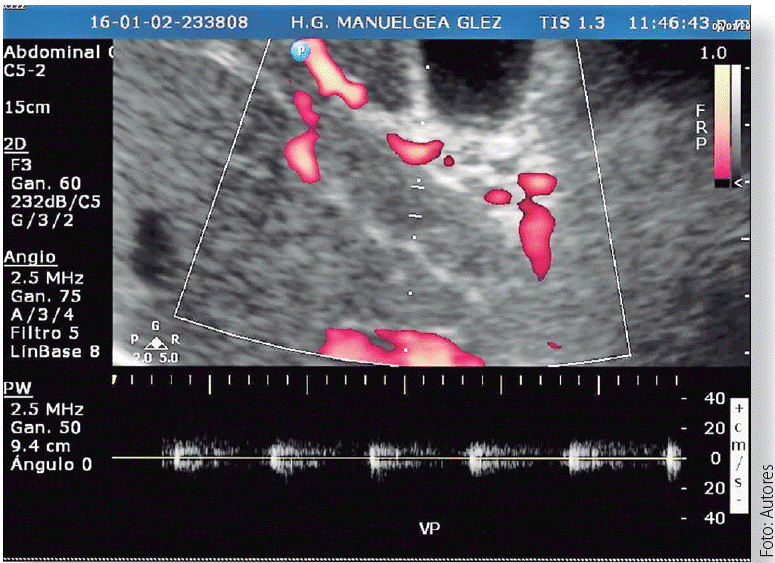

Аортальная регургитация: диагностика с использованием допплера